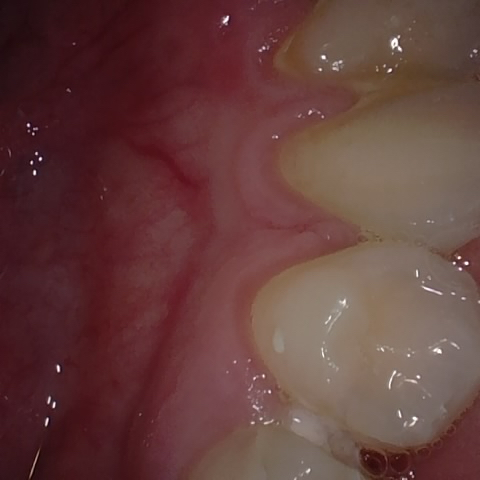

Annotated as "Good"

Original Image Rendering Image